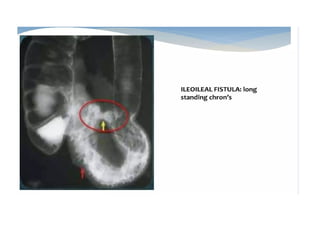

• Crohn's disease is a transmural granulomatous inflammatory

process of the bowel wall characterized by waxing and waning

course and discontinuous involvement of the bowel, which can

be complicated by fistulae and abscesses.